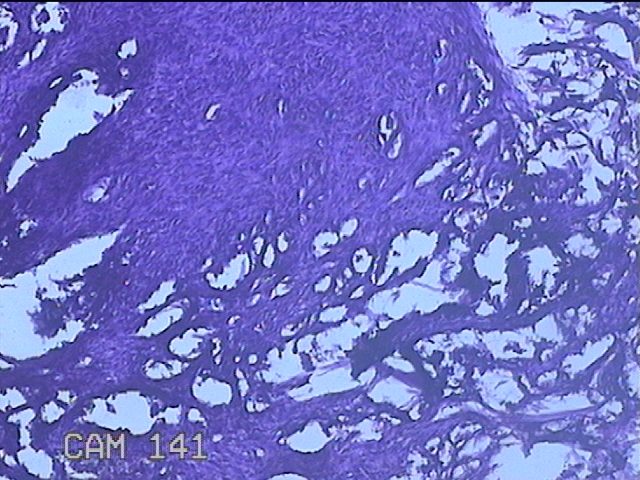

右侧前臂结节

性别

女

年龄

38岁

临床诊断

皮下结节

一般病史

发现右侧前臂结节1年余。

标本名称

大体所见

灰白粉红色带皮肤样组织0.8x0.7x0.3cm一块,表面带梭形皮肤0.8x0.7cm,皮下见结节0.8x0.5x0.3cm一个,切开结节呈实性,切面灰白粉红色,质软。